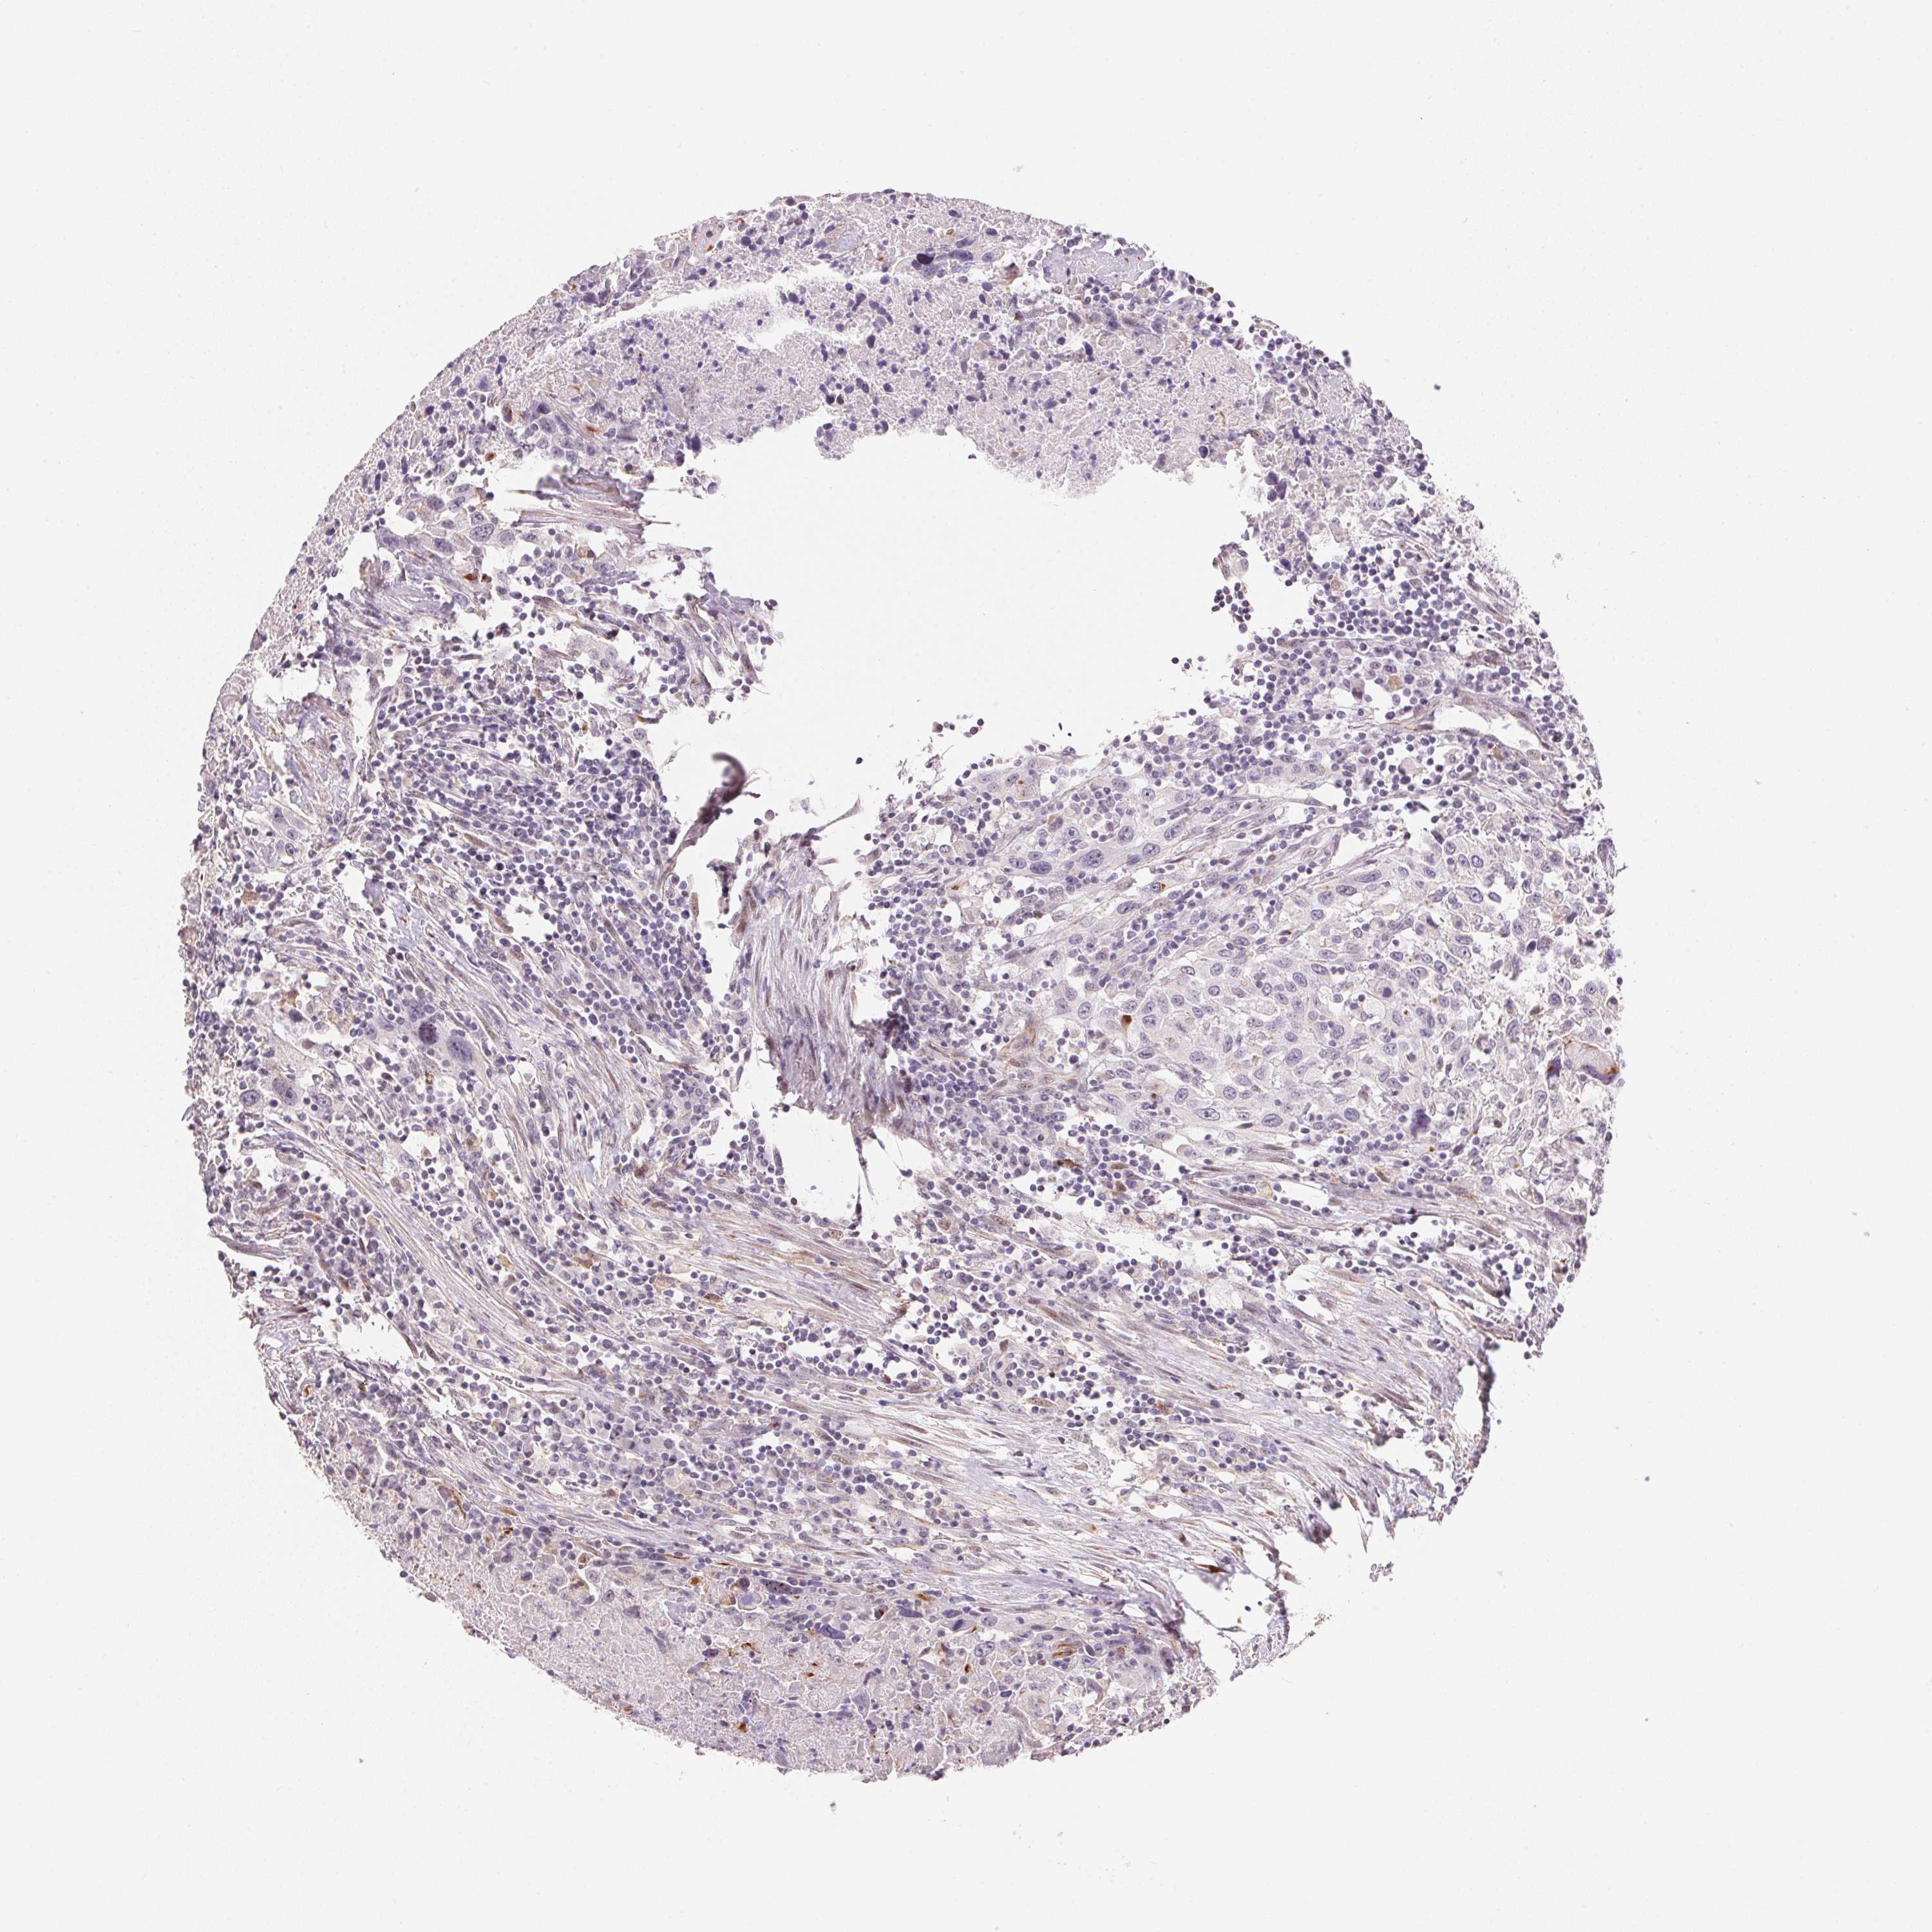

UROTHELIAL CANCER - Protein expressioni

A mouse-over function shows sample information and annotation data. Click on an image to view it in a full screen mode. Samples can be filtered based on level of antibody staining by selecting one or several of the following categories: high, medium, low and not detected. The assay and annotation is described here.

Note that samples used for immunohistochemistry by the Human Protein Atlas do not correspond to samples in the TCGA dataset.

Antibody stainingi

Antibody staining in the annotated cell types in the current human tissue is reported as not detected, low, medium, or high, based on conventional immunohistochemistry profiling in selected tissues. This score is based on the combination of the staining intensity and fraction of stained cells.

Each image is clickable and will lead to virtual microscopy that enables deeper exploration of all samples and also displays staining intensity scores, fraction scores and subcellular localization as well as patient and tissue information for each sample.

Antibody HPA005495

Antibody HPA064686

Staining

High

Medium

Low

Not detected

Intensity

Strong

Moderate

Weak

Negative

Quantity

>75%

75%-25%

<25%

None

Location

Nuclear

Cytoplasmic/membranous

Cytoplasmic/membranous,nuclear

Urothelial carcinoma, High grade

Urothelial carcinoma, Low grade

Urothelial carcinoma, NOS